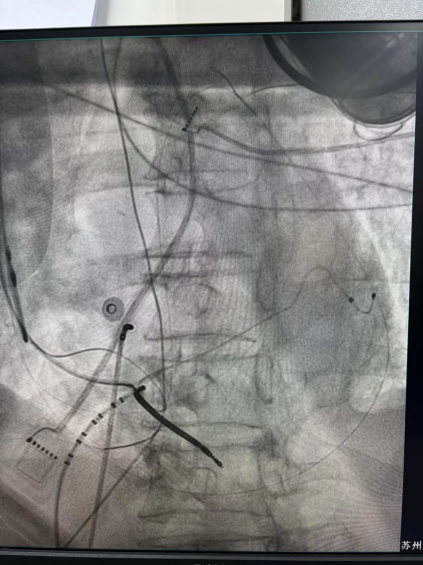

王林林主任医师谨慎操作,成功进入心外膜达到病变位置。术中,患者反复自发多形态室速,且转为室扑,同时出现血流动力学不稳定,需多次电除颤方能终止发作,标测难度极大。这就要求医疗团队必须在有限的标测时间内精准定位室速消融靶点,并结合心内外膜基质特征制定消融策略。经针对性消融后,患者未再自发室速,且室性早搏转为单一形态,经判定为右心室乳头肌来源,随即予以一并消融。术后经心室程序电刺激验证,室速未再被诱发。

右心室后组乳头肌室早电位